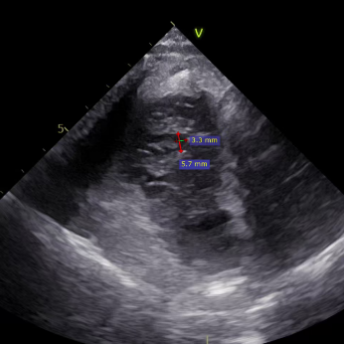

Ultrasound Evaluation:

- Regurgitation orifices located at the anteroseptal and posteroseptal commissures, with a 5.7×3.3mm gap detected in the center.